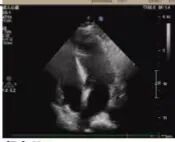

術(shù)后超聲

術(shù)后病理顯示,患者左房腫瘤為良性黏液瘤,完整切除后無需后續(xù)治療。經(jīng)過10天的康復(fù)治療,老人順利出院。這一案例中,多學(xué)科團(tuán)隊(duì)通過術(shù)前風(fēng)險(xiǎn)分層、術(shù)中精密協(xié)作、術(shù)后個(gè)體化護(hù)理,為高齡復(fù)雜心臟疾病患者的救治積累了臨床經(jīng)驗(yàn)